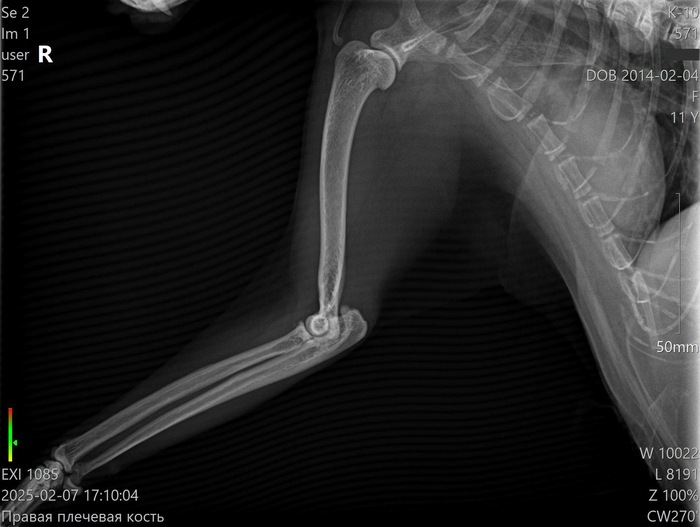

Когда кошка (14 лет, питание куриной печенью) захромала мы обратились в клинику где уже лечили царапины пёселя. Ветеринар не увидела показаний к рентгену ("если бы был перелом, кошка бы не опиралась на лапу") сказав, что это ушиб или старческие изменения посоветовала комплекс для суставов и обезболивающие.

Через неделю, улучшений не было и мы съездили в ту же клинику, где уже сделали рентген. В тот день приём вела другой ветеринар. Она сразу сказала, что не дока по чтению и расшифровке снимков кошачьих лап. Девушка попыталась сравнить снимок с примером из большого рентгенологического атласа и её внимание привлекла головка лучевой кости, которая была вроде бы слишком в стороне.

Поставилии диагноз: "вывих головки лучевой кости в лучезапястном суставе" и направили к травмотологу.

По вердикту травмотолога (третьего ветеринара) кости в порядке и на своих местах. Проблема в "локтевом" суставе где непонятное новообразование или киста/капсула из-за отёка сустава.

Но всё-же, учитывая размеры города, выбор ветеринаров не то, чтобы прям большой. Поэтому, мне бы хотелось узнать ещё "четвёртое" мнение со стороны. Всё-таки запасных кошек у нас не имеется, а каждый ветеринар свой диагноз ставит пока она продолжает хромать.

Действительно ли лучевая кость должна быть так сильно в стороне?